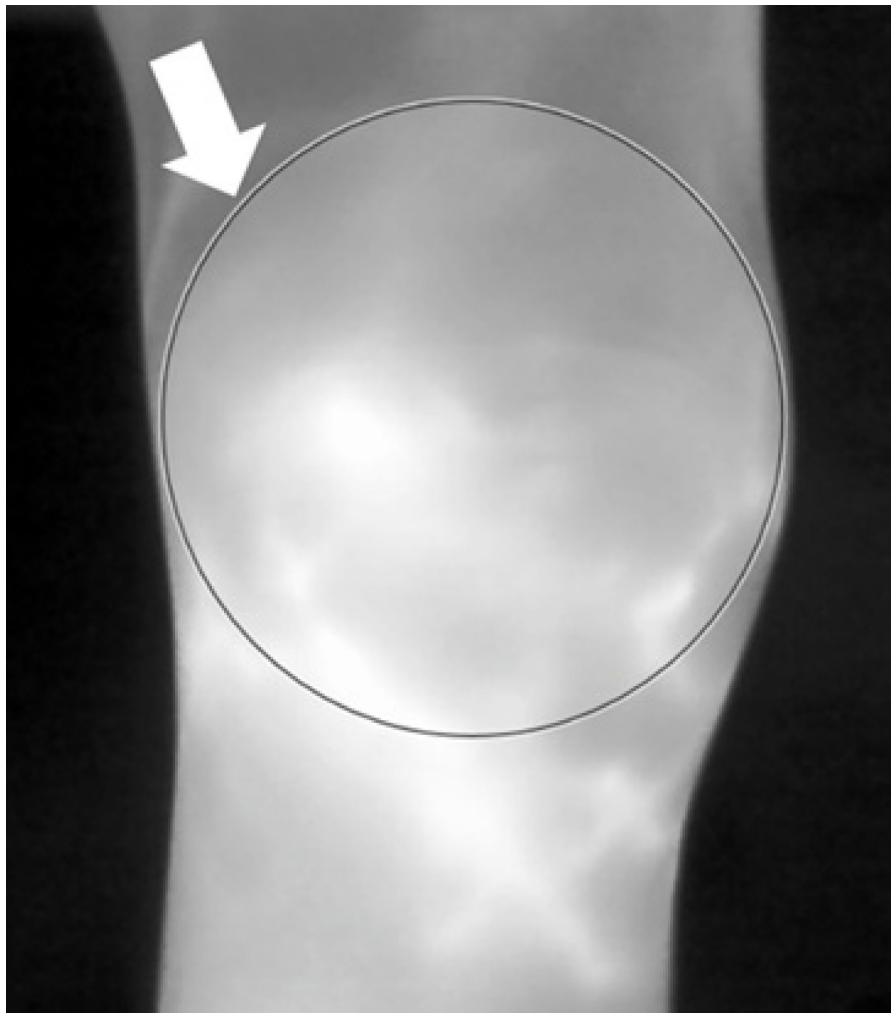

研究团队采用横断面设计,对95例RA患者的190个膝关节同时进行标准化热成像和超声检测。关键技术包括:1)使用FLIR T640热像仪(灵敏度<30mK)在23°C恒温环境下采集膝部三个角度(外侧/前侧/内侧)的热图;2)采用Mindray M9超声仪按EULAR标准评估膝关节上隐窝的GS和PD信号;3)通过手动划定感兴趣区域(ROI)获取最小(T-min)、最大(T-max)和平均(T-avg)温度值;4)采用Spearman相关性分析和ROC曲线评估诊断效能。

在识别PD阳性方面,左膝前侧T-avg表现最佳(AUC=0.82),当截断值为31.6°C时,敏感性和特异性分别为85.7%和79.0%。对于GS≥2分的识别,左膝内侧T-avg同样展现出0.82的AUC值。值得注意的是,不同膝关节部位的最佳参数各异,提示全面扫描三个角度的临床价值。